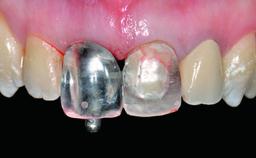

Replacement of a Failing Upper Left Central Incisor: Immediate Placement of an RC Bone Level Implant and Provisionalization

Abutment Type CAD/CAM

Prosthesis Type FDP

Loading Protocol Immediate

Retention Cemented, with prosthesis margin < 3mm submucosal Cemented, with prosthesis margin < 3mm submucosal

Provisional Implant-Supported Prosthesis Prosthodontic margin < 3 mm apical to mucosal margin Prosthodontic margin < 3 mm apical to mucosal margin